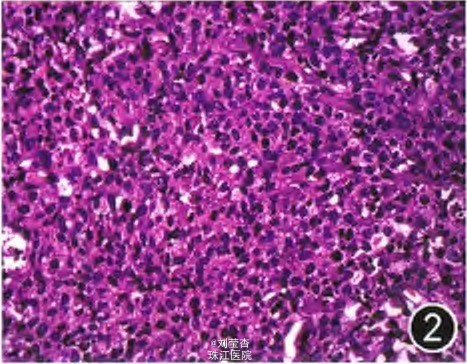

体格检查:皮肤科检查:全身皮肤可见多发形状不规则的结节,边界清楚,直径0.5—2.5 cm,质韧,活动度可,表面皮肤有棕褐色色素沉着,压之不褪色,Darier征阳性,尼氏征(一),全身皮肤未见水疱,无溃疡。 实验室检查:TORCH检查阴性,输血前检测甲肝、乙肝、丙肝、梅毒、艾滋病病毒抗体均阴性。体液免疫功能监测正常。血培养:无细菌生长。染色体报告:46XY。腹部彩色超声示:全身皮下多发低回声占位,肝、胆、脾、腹部未见异常。胸部x线片、颅脑磁共振成像(MRI)未见异常。早产儿视网膜病(ROP)检查:双眼视网膜血管发育近锯齿缘,周边较多出血灶。皮肤结节病理及免疫组织化 学检查:表皮未见明显异常,真皮浅中层中可见短梭形及卵圆形细胞浸润,吉姆萨染色:细胞质内可见紫蓝色异染颗粒;免疫组织化学:CIM3+++、LCA+++、lys+++、CD68(kpl)+++、CD4+、CDll7个别细胞+、髓过氧化物酶(MPO)+或一,CDla、S-100、CD56、TdT、CD20、pad-5、CD3、CD7均阴性、Ki67标记指数约80%。

诊断:新生儿皮肤肥大细胞增生症一结节型 给予赛庚啶片口服治疗。